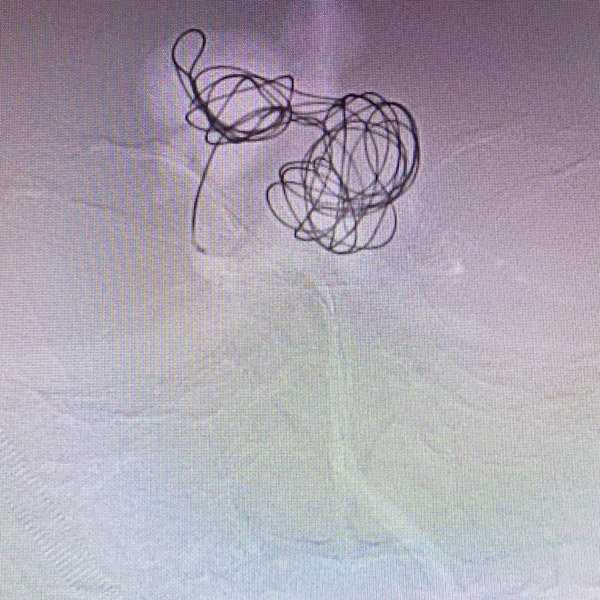

近日,一名7歲女性患兒因“突發意識障礙”,由外院急診轉至我院治療。通過急診CT檢查發現該患兒松果體區巨大占位并合并腦室血腫行成 ;急診腦血管造影明確為:大腦大靜脈球瘤。

我院迅速組織多學科MDT(神經外科、兒科ICU、放射介入科、麻醉科、手術室)討論制定詳細治療方案,征得家屬理解和簽字同意手術后,決定由神經外科血管介入組及顱底內鏡組進行聯合急診手術治療。神經介入醫師經股動脈置管行“彈簧圈+Onyx-18膠”致密栓塞靜脈球瘤控制出血,同時在高清神經內鏡輔助下行“腦室內鑄型血腫清除術”。